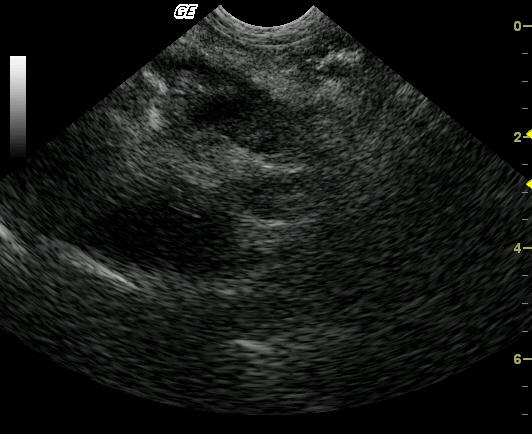

This 6-year-old Maltese presented for diarrhea, poor appetite, and lethargy immediately prior to the sonogram with a history of acute vomiting 2 weeks prior that had resolved without intervention. The patient also presented concurrently with acute anal sacculitis and dermal hot spots. Outpatient therapy with antibiotics proved mildly effective. CBC and blood chemistry analysis demonstrated a normal complete blood count and moderately elevated amylase, moderately elevated lipase, and moderately elevated SAP. Mild hypoalbuminemia was also present initially. A second analysis revealed similar values regarding amylase, lipase, and SAP with new moderately elevated cholesterol and moderately elevated triglycerides and moderate hypoalbuminemia.